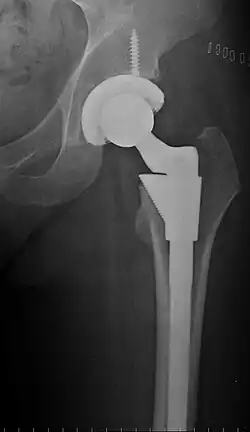

Intraoperative acetabular fracture

Intraoperative fractures may occur. After surgery, bones with internal fixation devices in situ are at risk of periprosthetic fractures at the end of the implant, an area of relative mechanical stress. Post-operative femoral fractures are graded by the Vancouver classification.[32][33]